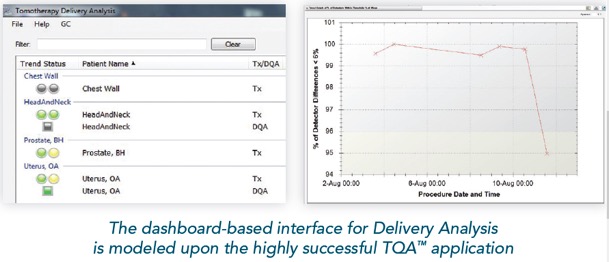

DELIVERY ANALYSIS™ - Εξατομικευμένος διαμετρικός έλεγχος ακτινοθεραπείας

I. Delivery Analysis

Το σύστημα Delivery Analysis επεξεργάζεται με τρόπο αυτόματο τα δεδομένα από την εκτέλεση της θεραπείας κάθε ασθενούς και ελέγχει αν κάθε συνεδρία αποδίδεται όπως έχει σχεδιαστεί.

- Για κάθε ασθενή, το Delivery Analysis ελέγχει τη σωστή λειτουργία του κατεθυντήρα πολλαπλών φύλλων χρησιμοποιώντας το σήμα του ενσωματωμένου ανιχνευτή του συστήματος TomoTherapy. Σε περίπτωση εμφάνισης διαφορών το σύστημα αυτόματα υπολογίζει την επίδραση τους στην κατανομή της χορηγούμενη δόσης και ειδοποιεί τον ακτινοφυσικό και τον ιατρό.

- Σε κάθε συνεδρία το σύστημα μετράει και επεξεργάζεται την ροή φωτονίων στην έξοδο του ασθενούς (exit fluence) για να εξασφαλίσει την σωστή εκτέλεση της θεραπείας από την πρώτη έως την τελευταία συνεδρία.

Εύχρηστο περιβάλλον εργασίας

- Το σύστημα Delivery Analysis αναλύει τα δεδομένα από την εκτέλεση της θεραπείας και τα παρουσιάζει με τρόπο άμεσο και ευανάγνωστο στους ακτινοφυσικούς και του ιατρούς του τμήματος. Το σύστημα ενσωματώνει εργαλεία για την λεπτομερή εξέταση όλων των επιμέρους στοιχείων της θεραπείας συμπεριλαμβανομένων της ακρίβειας τοποθέτησης του ασθενούς, την επίδοσης του συστήματος TomoTherapy κτλ.

Δοσιμετρικός έλεγχος πριν την εκτέλεση της θεραπείας

Το σύστημα Delivery Analysis παρέχει τα απαραίτητα εργαλεία για τον ποιοτικό έλεγχο των πλάνων θεραπείας κάθε ασθενούς. Συγκεκριμένα:

Το σύστημα Delivery Analysis παρέχει τα απαραίτητα εργαλεία για τον ποιοτικό έλεγχο των πλάνων θεραπείας κάθε ασθενούς. Συγκεκριμένα:

- πριν την έναρξη της θεραπείας εκτελείται μια διαδικασία δοσιμετρικού ποιοτικού ελέγχου,

- το σύστημα Delivery Analysis συλλέγει τα δεδομένα από τον ενσωματωμένο ανιχνευτή του συστήματος και

- ανακατασκευάζει την μετρούμενη κατανομή δόσης στις εικόνες αξονικής τομογραφίας του ασθενή και την συγκρίνει με αυτή του πλάνου θεραπείας

Ποιοτικός έλεγχος της ακρίβειας χορήγησης της θεραπείας

- Κατά την διάρκεια εκτέλεσης κάθε συνεδρίας και για κάθε ασθενή το σύστημα Delivery Analysis μετράει αυτόματα με τον ενσωματωμένο ανιχνευτή την ροή των φωτονίων στην έξοδο του ασθενούς

- Το σύστημα Delivery Analysis αναλύει και επεξεργάζεται αυτόματα την ροή των φωτονίων στην εξόδου του ασθενούς ώστε να εξασφαλίσει την σωστή εκτέλεση κάθε συνεδρίας της θεραπευτικής αγωγής του κάθε ασθενούς.